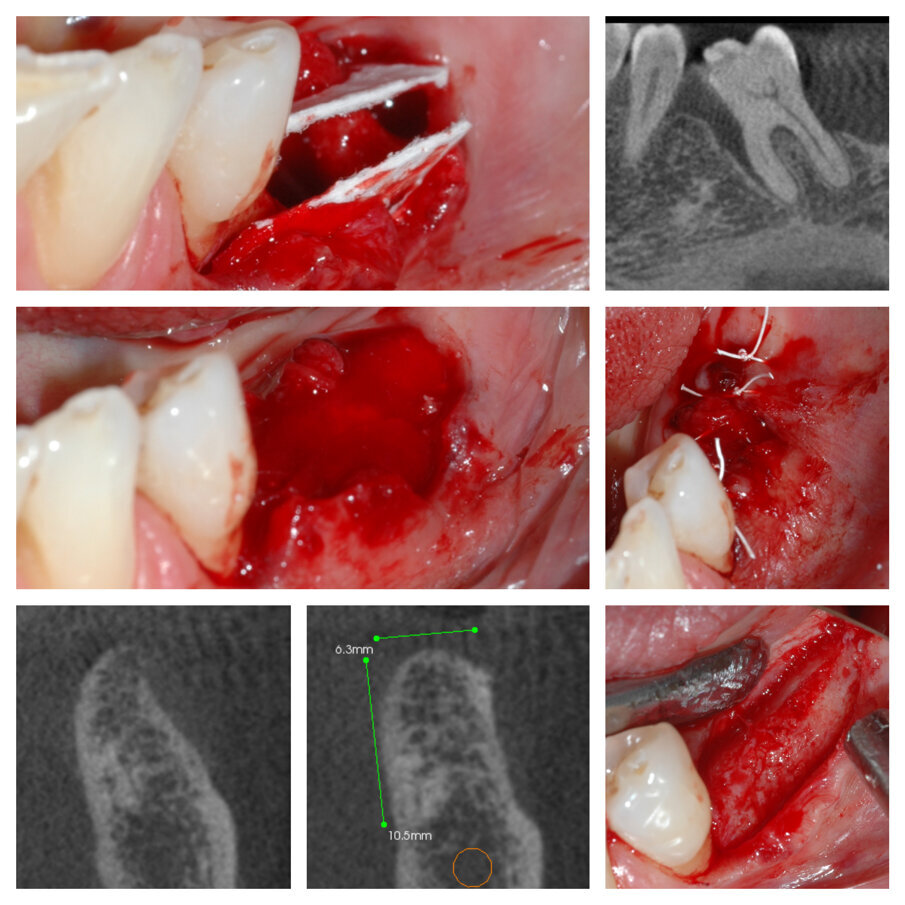

Fig. 3a_Tecnica S.A.T. applicata in zona 44-45-46.

Fig. 3b_Cambiamento dei tessuti a 27 giorni.

Fig. 3c_CBCT pre intervento e dopo 6 mesi a confronto.

Fig. 3d_Qualità del tessuto neoformato e posizionamento implantare.

Fig. 4a_Elemento 36 mesio inclinato, deficit orizzontale in zona 35 risolto con tecnica S.A.T.